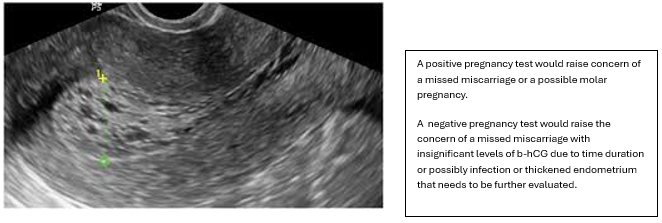

Another example could be a heterogenous appearance to a thickened endometrium that fills the entire endometrial cavity. The client claims she is 8 weeks by LMP. If the pregnancy test is positive, she could have had a missed miscarriage (a miscarriage that hasn’t been evacuated from the uterus) or a molar pregnancy. If the pregnancy test is negative, she could possibly have a missed miscarriage, as time has passed, the hormone level has dropped to insignificant levels. Another possibility is a thickened heterogenous endometrium due to hormonal issues or infection, not pregnancy-related.